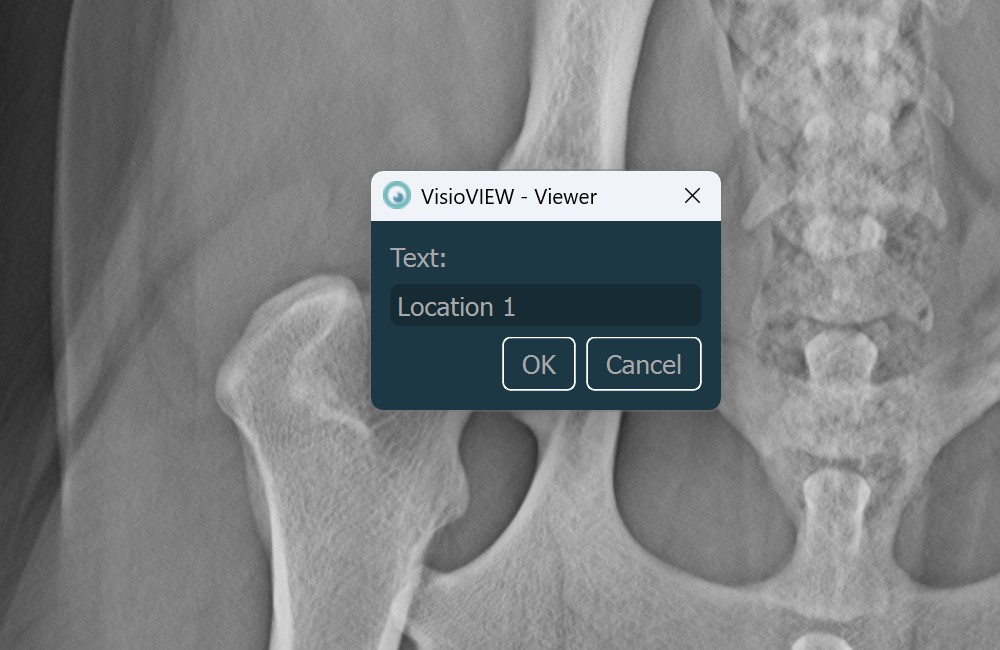

Text Tool¶

Label and comment important information on the image by using the Text Tool. The text is always assigned to a point that can be later modified by using the Select/Move Item tool.